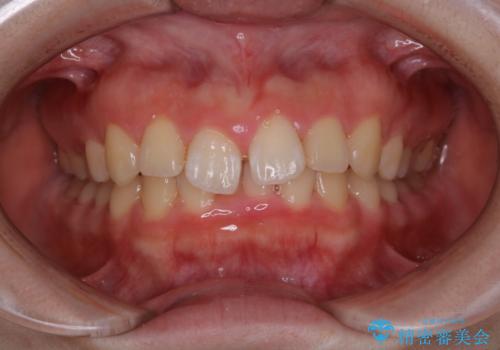

1. 矯正治療前にPMTCで口元のケアの治療前